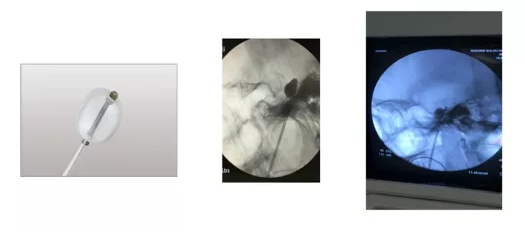

经皮穿刺半月神经节球囊压迫术(PBC)

随着微创介入技术的发展, “微创球囊压迫术” 已成为三叉神经痛治疗的主要手术方式。操作简单,无痛、无紧张情绪(病人舒适感强)、不需要术中病人配合。

适用于:

1. 部分三叉神经痛病人因高龄、经济困难、不能耐受或恐惧开颅微血管减压手术;

2. 微血管减压术、射频治疗、伽马刀等治疗无效或复发的病人;

3. 影像学检查行微血管减压手术相对困难或风险较大。